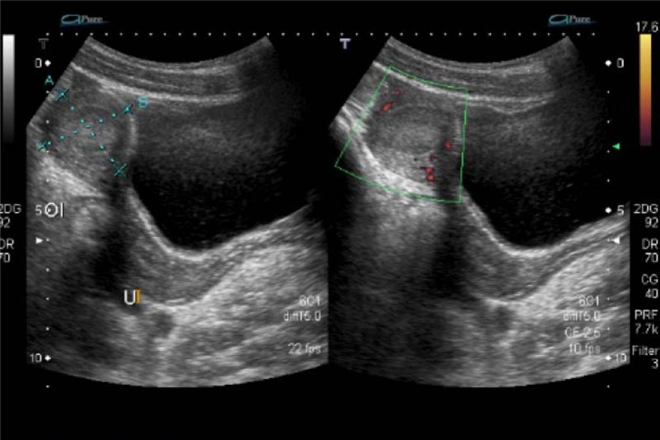

Exploración ultrasonográfica renal

La ultrasonografía del sistema urinario es una herramienta diagnostica de apoyo en el ejercicio de la profesión médica, pues permite un diagnóstico y tratamiento oportuno de las patología renales a través de la evaluación de las estructuras anatómicas del paciente mediante sonido. Además es un técnica que se puede usar